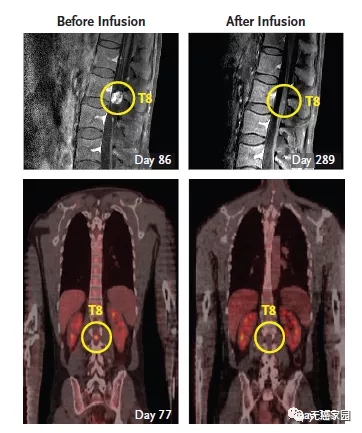

3、脑室内注射CAR-T细胞,首次消灭实体瘤

2016年12月,NEJM曾报道过1例利用CAR-T技术治疗脑胶质瘤的案例。一名50岁的男性,确诊为高级别脑胶质瘤,先后做了手术、放疗、替莫唑胺化疗等常规治疗,6个月后疾病复发。这时他参加了一项临床试验,接受靶向IL13Rα2的CAR-T治疗。不过这个疗法,有些“惊悚”。

主管医生通过核磁共振检查发现:这位病友脑部有5个病灶;因此,先通过手术切掉其中的三个大的,还剩下两个较小的由于位置深,无法切除。主管医生就给他的病灶处直接插了一个管子,然后通过这个管子,把CAR-T细胞打了进去,分3个批次,进行了多次的细胞回输。最终,肿瘤完全消失,疗效维持了8个月左右。

第二轮CAR-T疗法结束后,Richard Grady脊索内肿瘤出现剧烈萎缩

目前,CAR-T疗法治疗脑瘤的前瞻研究国内也在积极的开展临床试验,大家可致电无癌家园医学部了解详情。